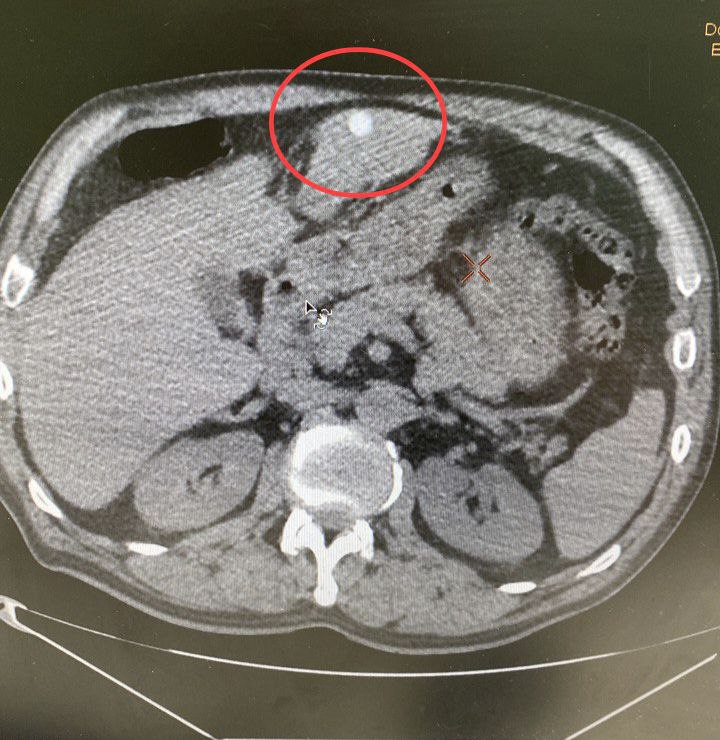

В Талдомскую больницу бригадой скорой помощи был доставлен 57-летний мужчина в тяжелом состоянии. Как выяснилось, в результате ссоры ему были нанесены выстрелы в упор из травматического оружия и нанесено 7 пулевых ранений. После проведенного обследования врачи диагностировали мужчине повреждение брюшной полости и печени. Также у пациента наблюдались раны мягких тканей грудной клетки, передней брюшной стенки, паховой области, бедра и кисти.

«В экстренном порядке мы провели оперативное вмешательство, в ходе которого удалили 7 пуль, затем провели обработку ран. Ситуация осложнялась массивным внутрибрюшным кровотечением. Для его остановки хирурги провели резекцию нежизнеспособных тканей печени. Общая кровопотеря составила 1 литр. В настоящее время жизни и здоровью пациента ничего не угрожает. Операция прошла успешно и заняла 2 часа», – рассказал врач-хирург Талдомской больницы Игорь Игнатчик.